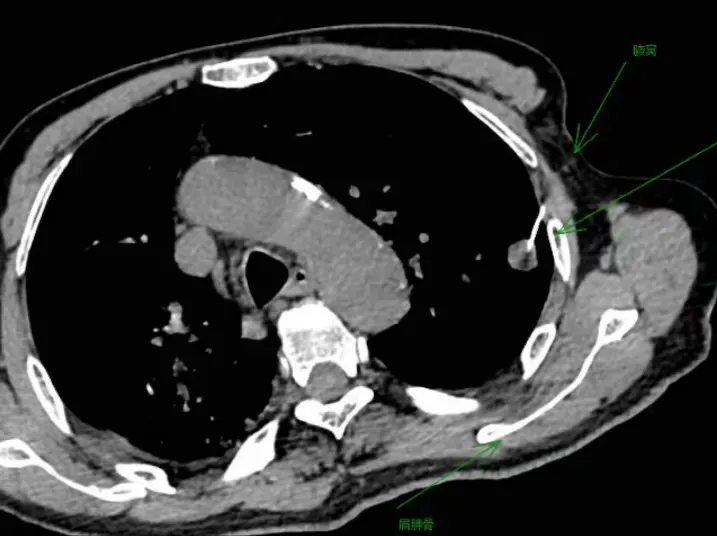

“当看到患者的CT片后,结节过小,不足1.3cm,穿刺路径上有肋骨、肩胛骨阻挡,而且患者正常呼吸时肺的活动度很大,需要一针到位,稍有不慎就会引发气胸风险,一旦气胸掩盖结节,穿刺将无法进行,给患者造成不可挽回的损伤。”

肺病科谢加利主任和副主任艾克东反复对比患者的CT图像,利用二维、三维重建技术,仔细分析患者病变的位置,辨别病变与血管、支气管等重要脏器之间的关系,充分做好术前准备,与患者及家属沟通并征得同意后,为患者实施CT引导下肺穿刺活检术。术中发现,由于体位的关系,病变位置有所变化,穿刺难度比预想的更大,从侧面根本无法进针。在谢加利主任的指导下,艾克东副主任临危不惧,结合CT引导,让患者取左侧垫高位,在腋窝选取进针路线,娴熟定位很快到达病灶,精准穿刺顺利取得病理组织,全程操作快、准、稳。术后病理诊断为腺癌,为患者下一步治疗提供了依据。